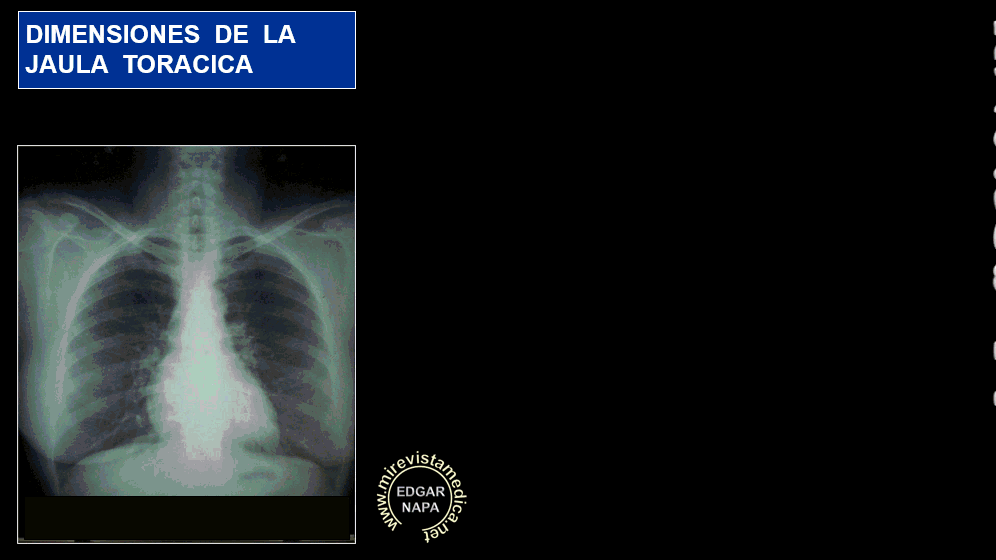

JAULA TORACICA. Elementos que la conforman:

- Costillas (24) .

- Esternon .

- Cartílagos Costales.

Su límite superior es trunco y se continúa con las estructuras del cuello .

Su limite inferior esta dado por el musculo Diafragma.